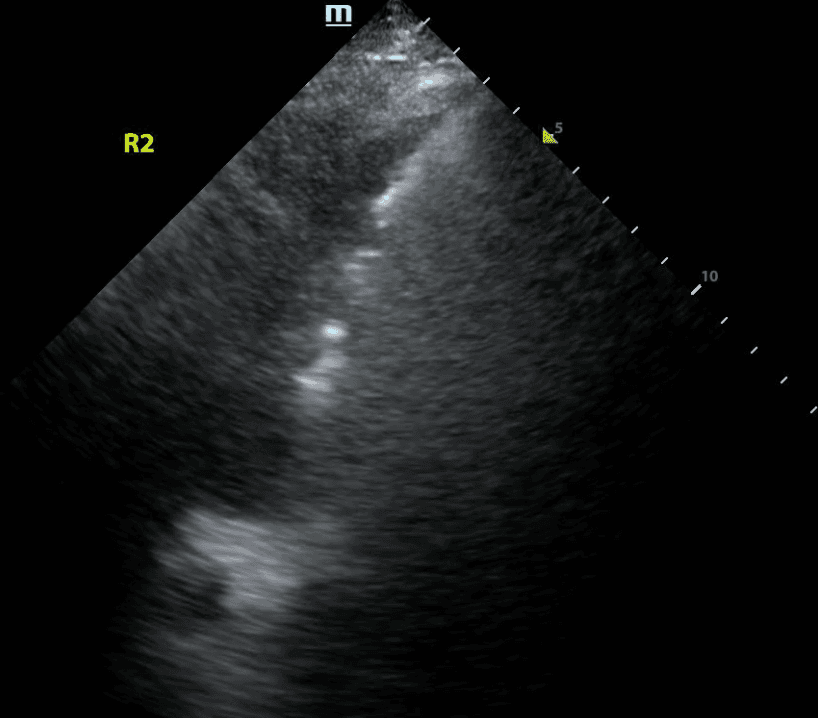

Recall that B lines are vertical hyperechoic artifacts originating from the pleural line that look similar to comet-tails.

B lines reflect interstitial syndrome and the number of B lines increase with decreasing air content in lungs and thus, increasing lung density. To narrow down this broad differential, one can evaluate whether the B lines are present in a diffuse or focal (clumped together) pattern, look at abnormal pleural line patterns and look for other features of abnormal lung on ultrasound.